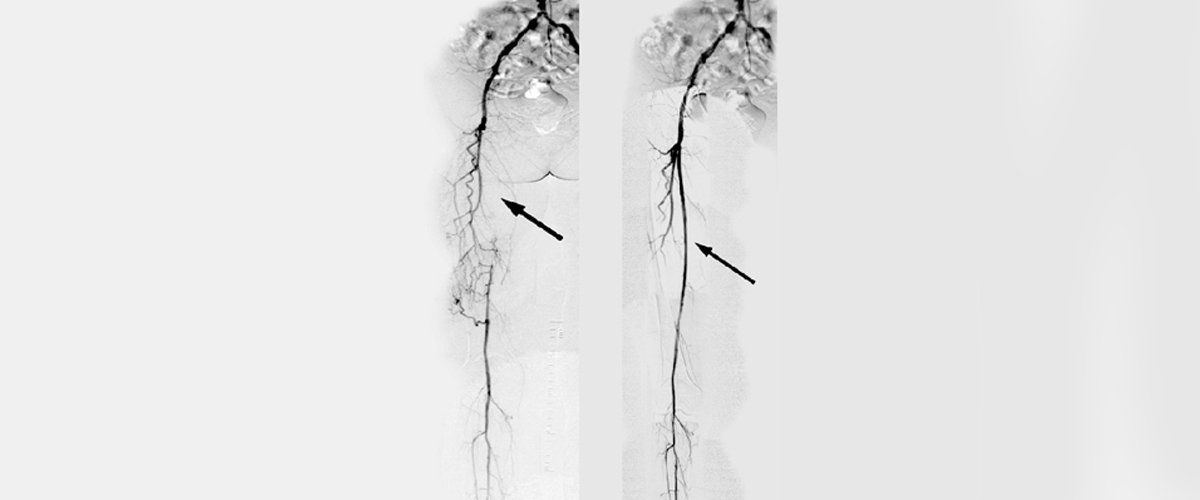

Dr. Patrick M. Tamim is certified vascular surgery. Trust in his expertise to help restore you back to health.

Our office can provide you with services that address your vascular needs. We will tailor your diagnostic testing, surgeries and medications to suit your specific needs. Rest easy knowing that we want what is best for you and your long- term health goals, and will work with you to help you reach those goals. Contact Patrick M. Tamim M.D. today for more information.